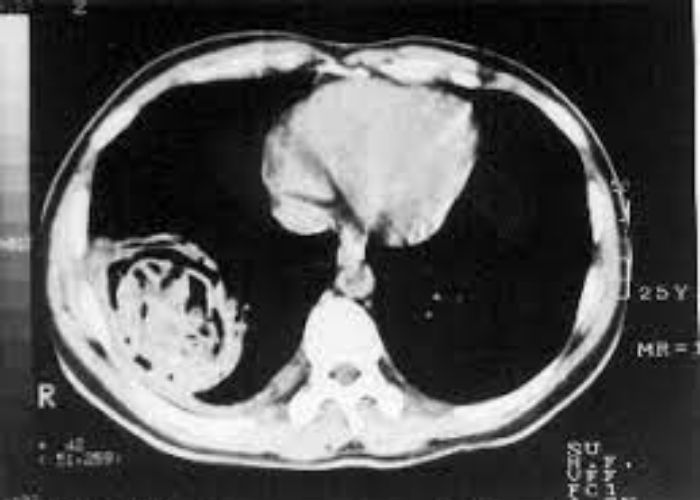

Echinococcus granulosus paraziti tarafından oluşturulan Hidyatik kist olarak bilinen, akciğer ve karaciğerde birçok kistten oluşan bir hastalıktır. Akciğerde 1-2 cm tek bir kistten 10-15 cm e ulaşan çok sayıda kiste kadar değişiklik gösterebilir.

Bilgisayarlı Tomografi ( BT ) ile tanı konulur. Aynı zamanda serolojik olarak kanda ekinokokal antikorlar saptanabilir.